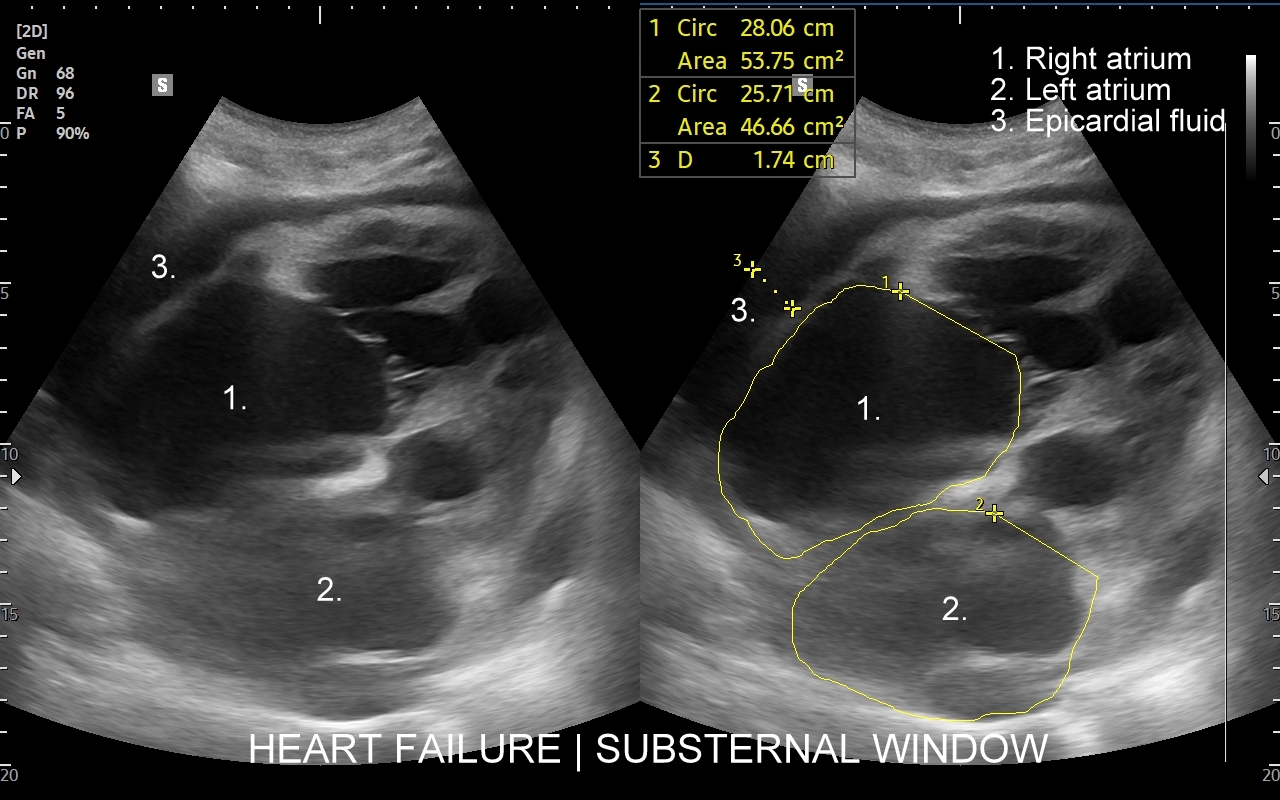

Badanie echokardiograficzne, nazywane także echo serca lub USG serca jest jedną z podstawowych metod diagnostyki kardiologicznej. W badaniu tym ocenia się zarówno morfologię narządu, jak i jego funkcję w postaci pomiarów wielkości jam serca, grubości mięśnia sercowego, czynności skurczowej oraz rozkurczowej lewej i prawej komory, oceny funkcji zastawek serca, wyglądu wsierdzia, osierdzia, a także w postaci pomiarów aorty, poszukiwania obecności patologicznych objawów sercowych związanych z chorobami innych narządów (np. choroby płuc, nadciśnienie tętnicze).